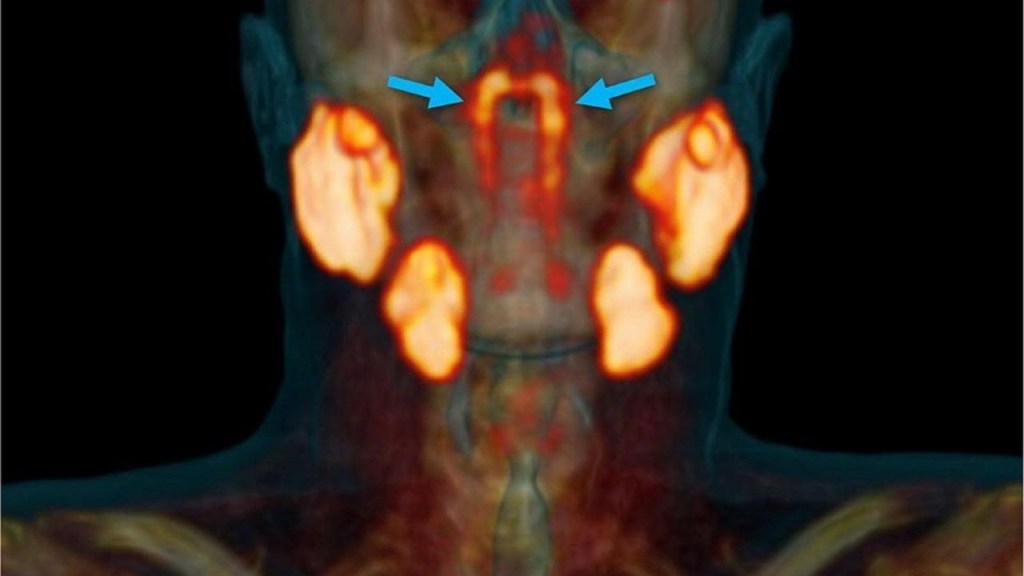

Científicos han descubierto un nuevo órgano: las glándulas salivales tubariales, un hallazgo sorprendente en la anatomía humana. Descubiertas en 2020 por investigadores de los Países Bajos, se ubican detrás de la nariz, en la unión con la garganta. Este descubrimiento redefine nuestro conocimiento médico y abre nuevas posibilidades para mejorar tratamientos contra el cáncer de cabeza y cuello.

Las estructuras que forman el nuevo órgano, de aproximadamente 1.5 pulgadas de largo, se encontraron en la zona donde la cavidad nasal conecta con la parte superior de la garganta. Posteriores escáneres realizados en más de 100 individuos confirmaron su presencia constante. Además, disecciones de dos cadáveres verificaron la existencia de estas glándulas.

El hallazgo de este nuevo órgano es notable porque constituye la primera adición a las glándulas salivales principales en siglos. Hasta entonces, se reconocían únicamente las parótidas, submandibulares y sublinguales. El descubrimiento de las tubariales demuestra que aún existen aspectos básicos de la anatomía humana por explorar.